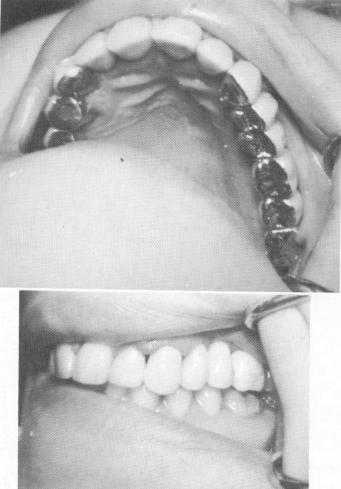

Fig. 13-54. Pin implants were driven through the openings in the template.

Fig. 13-55. The superstructure was cemented over the template after the triplant pins were affixed with acrylic.